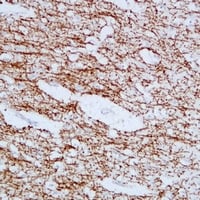

(Immunohistochemical analysis of MBP staining in human brain formalin fixed paraffin embedded tissue section. The section was pre-treated using heat mediated antigen retrieval with sodium citrate buffer (pH 6.0). The section was then incubated with the antibody at room temperature and detected using an HRP conjugated compact polymer system. DAB was used as the chromogen. The section was then counterstained with haematoxylin and mounted with DPX.)